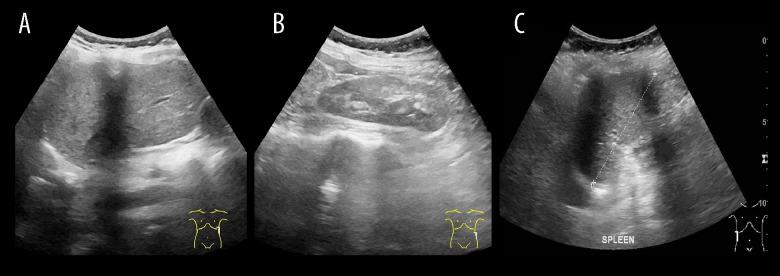

BACKGROUND Mayer-Rokitansky-Kuster-Hauser (MRKH) syndrome is a complex disorder of the female reproductive system that results in an absent uterus and vagina. MRKH syndrome can be an isolated anomaly (typical) or accompanied by other organ anomalies (atypical). Due to the similarity of symptoms with other congenital gynecological diseases, imaging modalities remain the most important tools in establishing the diagnosis by visualizing internal genital and detecting possible organ malformations. CASE REPORT We present a very rare case of a female with primary amenorrhea. Pelvic magnetic resonance imaging (MRI) showed the absence of a uterus and vagina with possible Mullerian remnants, as well as an incidental finding of a right ectopic kidney. Abdominal ultrasonography and chest X-ray showed that the patient also had situs inversus totalis. CONCLUSIONS MRKH syndrome may be associated with situs inversus totalis due to possible early embryologic malformations causing both conditions; however, the exact mechanism is still unknown. This report should serve as a more recent attempt to question whether situs inversus totalis is related to MRKH and to emphasize the importance of imaging modalities, especially MRI, in establishing the diagnosis of MRKH syndrome and the associated malformations.

我们介绍了一例女性原发性闭经的极罕见病例。盆腔磁共振成像(MRI)显示子宫和阴道缺失,可能有苗勒管残余物,以及右侧异位肾的意外发现。腹部超声和胸部 X 线检查显示患者还患有全内脏转位。